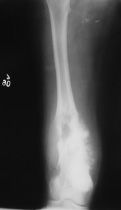

Klasik osteosarkom uzun kemiklerde kötü sınırlı, kemik yıkımına neden olan litik/sklerotik görünümlü lezyonlardır. Periostta kemiğe dik açıda oluşan kemik oluşumu (batan güneş manzarası) patogonomiktir. Yumuşak doku komponenti eşlik eder. BT kemik içerisindeki patolojileri göstermede yeterlidir. MRI ise yumuşak doku yayılımını, damar ve sinirin tutulup tutulmadığını, fiz hattının (büyüme kıkırdağı) etkilenip etkilenmediğini, komşu eklemin tutulup tutulmadığını, skip metastazların olup olmadığını ve uygun biyopsi yerinin belirlenmesinde yardımcıdır.

Radyolojik incelemede permeatif ve infiltratif kemik destüksiyonu vardır. Diafizde soğan halkaları tarzında periost reaksiyonu görülür. MRI incelemesinde yumuşak doku komponenti ve içerisinde nekroz alanlarının olup olmadığı, lezyonun kemik içerisine yayılımı, skip metastazlarının olup olmadığı, eklem ve komşu damar ve sinirlerin etkilenip etkilenmediği değerlendirilir. Kemik sintigrafisi tümörün aktivitesi ve metastazların varlığının değerlendirilmesi için kullanılır. Kesin tanı biyopsi ile konur.